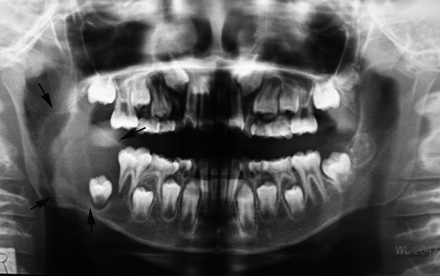

10歳 男児

X-pでは顎骨内に単房性の嚢胞様透過像を示すエナメル上皮腫の亜型。埋没歯をともなうことがあり画像のみでは含歯性嚢胞や他の嚢胞性病変との鑑別は難しい

X-pはdentigenous cystを思わせる像だが, 上皮の性状が異なる。